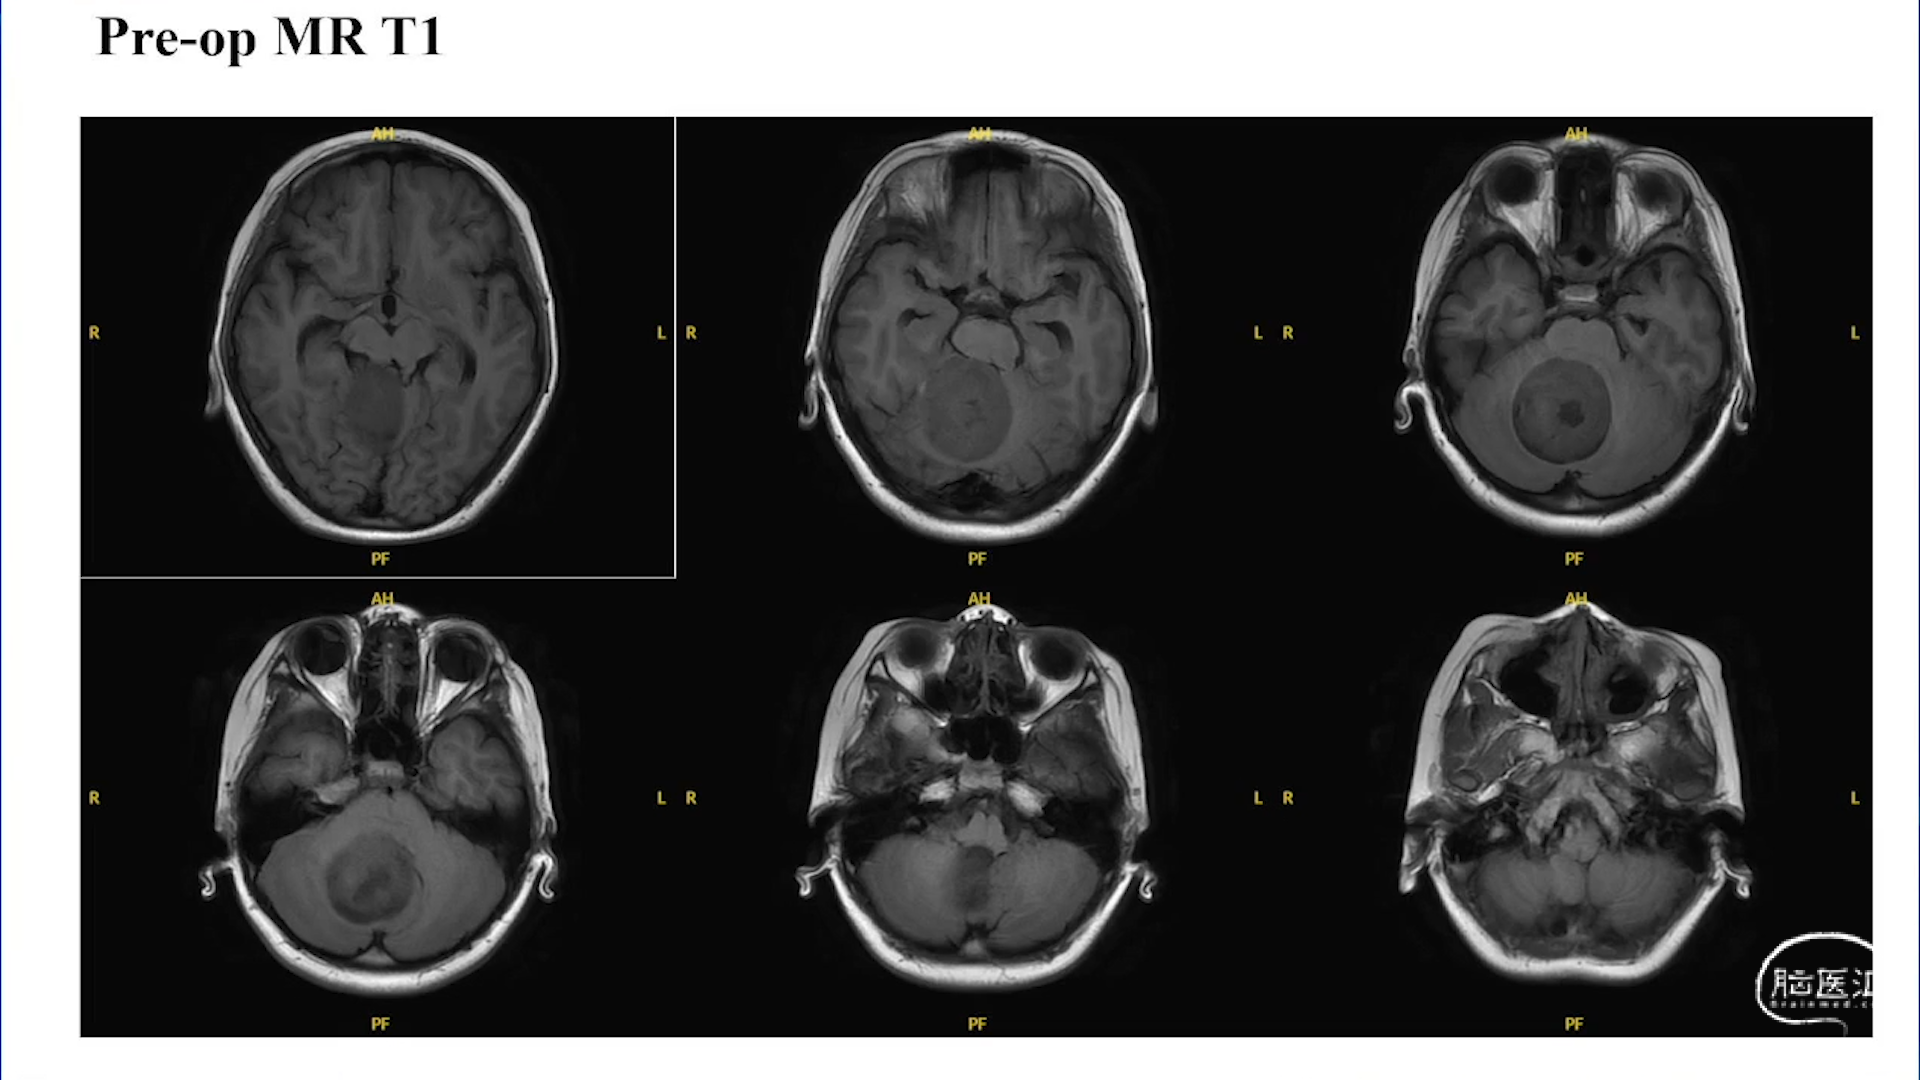

小脑星形细胞肿瘤